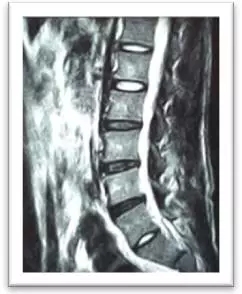

(术前)

刘志安副院长经查看MRI(核磁共振成像)结果后,显示小姚腰5/骶1椎间盘突出,髓核左下方游离,情况已经比较严重,遂收住入院。